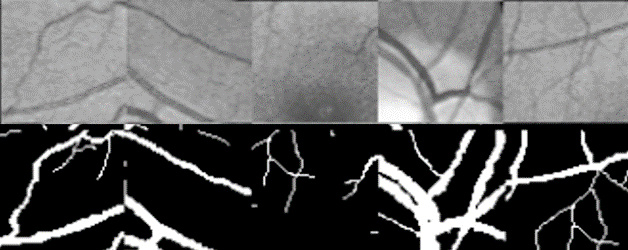

The original image, predicted probability image, predicted binary image and groundtruth

CHASE_DB1: